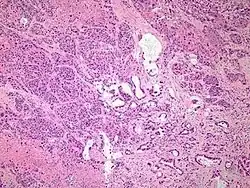

Micrographs of normal pancreas, pancreatic intraepithelial neoplasia (precursors to pancreatic carcinoma) and pancreatic carcinoma, H&E stain

Exocrine cancers are thought to arise from several types of precancerous lesions within the pancreas, but these lesions do not always progress to cancer, and the increased numbers detected as a byproduct of the increasing use of CT scans for other reasons are not all treated.[3] Apart from pancreatic serous cystadenomas, which are almost always benign, four types of precancerous lesion are recognized.

The first is pancreatic intraepithelial neoplasia (PanIN). These lesions are microscopic abnormalities in the pancreas and are often found in autopsies of people with no diagnosed cancer. These lesions may progress from low to high grade and then to a tumor. More than 90% of cases at all grades carry a faulty KRAS gene, while in grades 2 and 3, damage to three further genes – CDKN2A (p16), p53, and SMAD4 – are increasingly often found.[2]